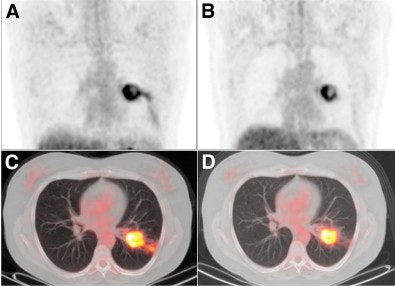

| Coronal FDG-PET images show a patient with carcinoma in the left lung. Maximum intensity projection (MIP) images before (A) treatment with erlotinib show a reduction in uptake (ΔSUVmax, -57%) and increase in necrosis of primary tumor after seven days (B) of treatment with erlotinib. The results are also noted in transverse PET/CT fusion images before (C) and after seven days (D) of erlotinib. After erlotinib treatment, the patient was operated on; the resected specimen contained 80% necrosis. Image courtesy of the Journal of Nuclear Medicine. |

FDG-PET/CT also revealed a median 40% necrosis in the resection specimens of treated patients. Among patients classified as metabolic responders, the median percentage necrosis was 70%, compared with a median 40% necrosis among metabolic nonresponders.

Aukema and colleagues found the median SUVmax at baseline FDG-PET/CT to be 11.0, while the median SUVmax after one week of erlotinib therapy was 9.3. In addition, six (26%) of the 23 cases had a partial response within one week, 16 patients (70%) had stable disease, and one patient (4%) had progressive disease.